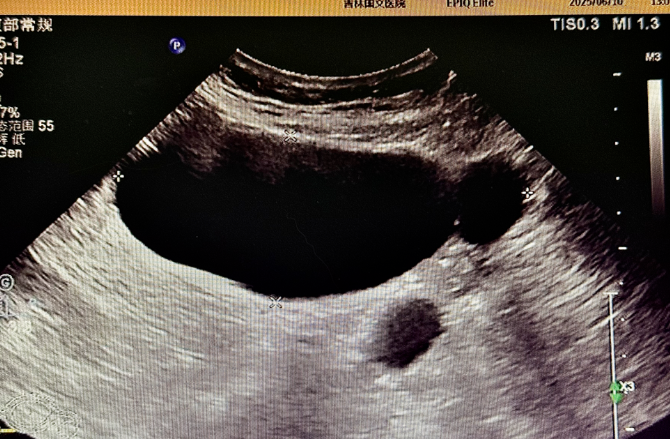

為精準(zhǔn)判斷病情,患者術(shù)前接受了多項(xiàng)影像學(xué)檢查:盆腔 MR 平掃顯示,腹腔內(nèi)存在囊性病灶,周圍伴有管狀影像,為病變定位提供了重要線索,下腹部 CT 進(jìn)一步提示輸卵管擴(kuò)張,腹盆腔內(nèi)可見低密度病灶,與 MR 結(jié)果相互印證,超聲檢查發(fā)現(xiàn)附件區(qū)有管狀無回聲結(jié)構(gòu),經(jīng)超聲科與婦科專家聯(lián)合會診,綜合分析后診斷為輸卵管積水。多項(xiàng)檢查數(shù)據(jù)的交叉驗(yàn)證,如同為醫(yī)生裝上 “透視眼”,讓隱藏的病灶無所遁形,為后續(xù)手術(shù)方案的制定打下了堅(jiān)實(shí)基礎(chǔ)。